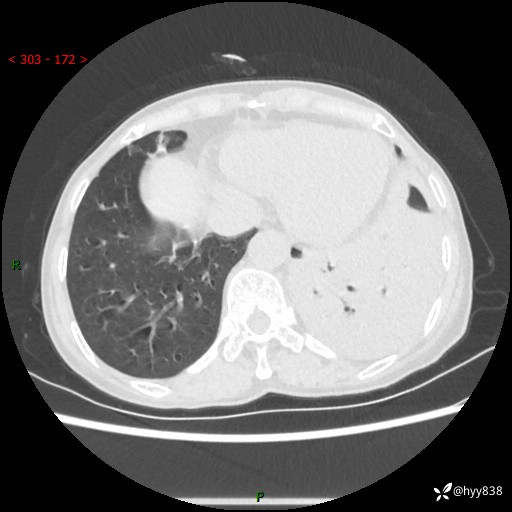

胸部CT平扫+增强